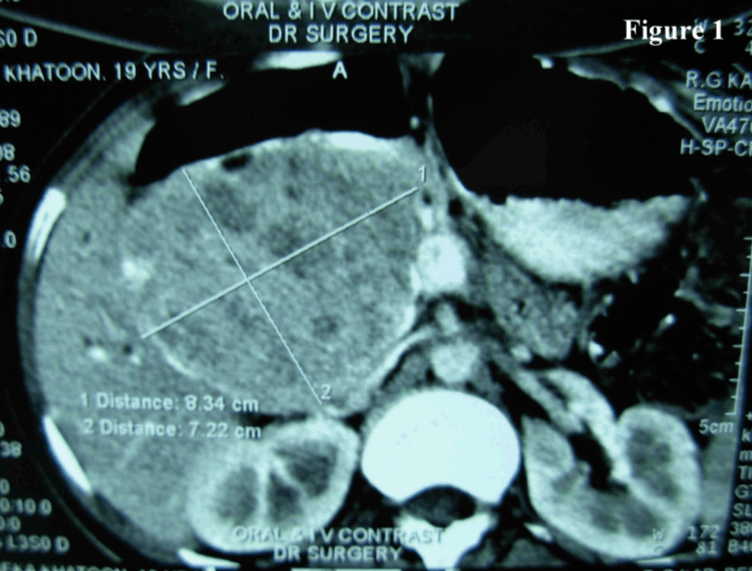

Histologically, the tumor cells were arranged in solid sheets, cords and pseudopapillae. Individual cells were uniform, medium sized, round with eosinophilic cytoplasm and bland nuclei with finely dispersed chromatin and inconspicuous nucleoli and some nuclei showed indentation. Mitotic figures were scanty. Vascular invasion was not noted. Surrounding capsule showed calcification (Figure 3). CD10 immunostain was done which showed focal positivity of moderate intensity. With these classic features a diagnosis of SPTP was offered.

Figure 3: Histopathology section showing tumor cells arranged in solid sheets, cords and pseudopapillae. Individual cells were uniform, medium sized, round, with eosinophilic cytoplasm and bland nuclei (H&E, x400).